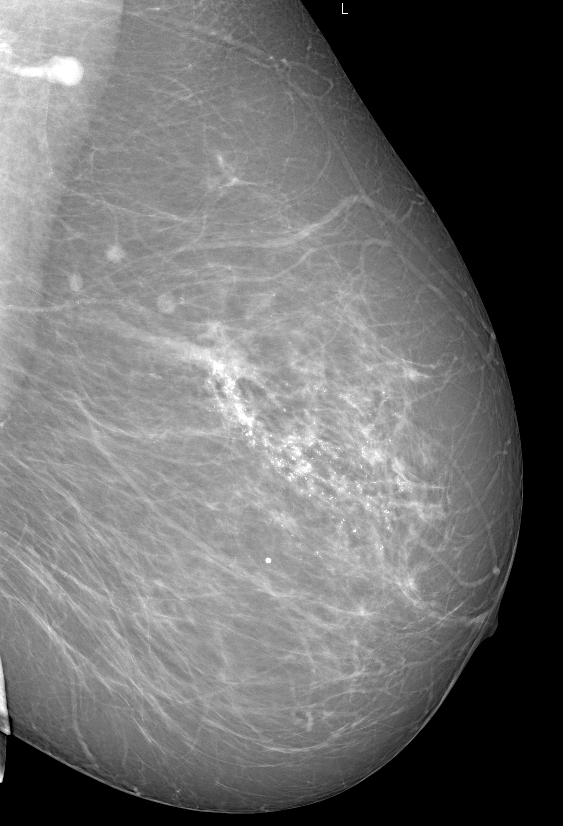

Аномалии молочной железы: медицинские примеры и визуализация

Раздел: Мудрость в деталях